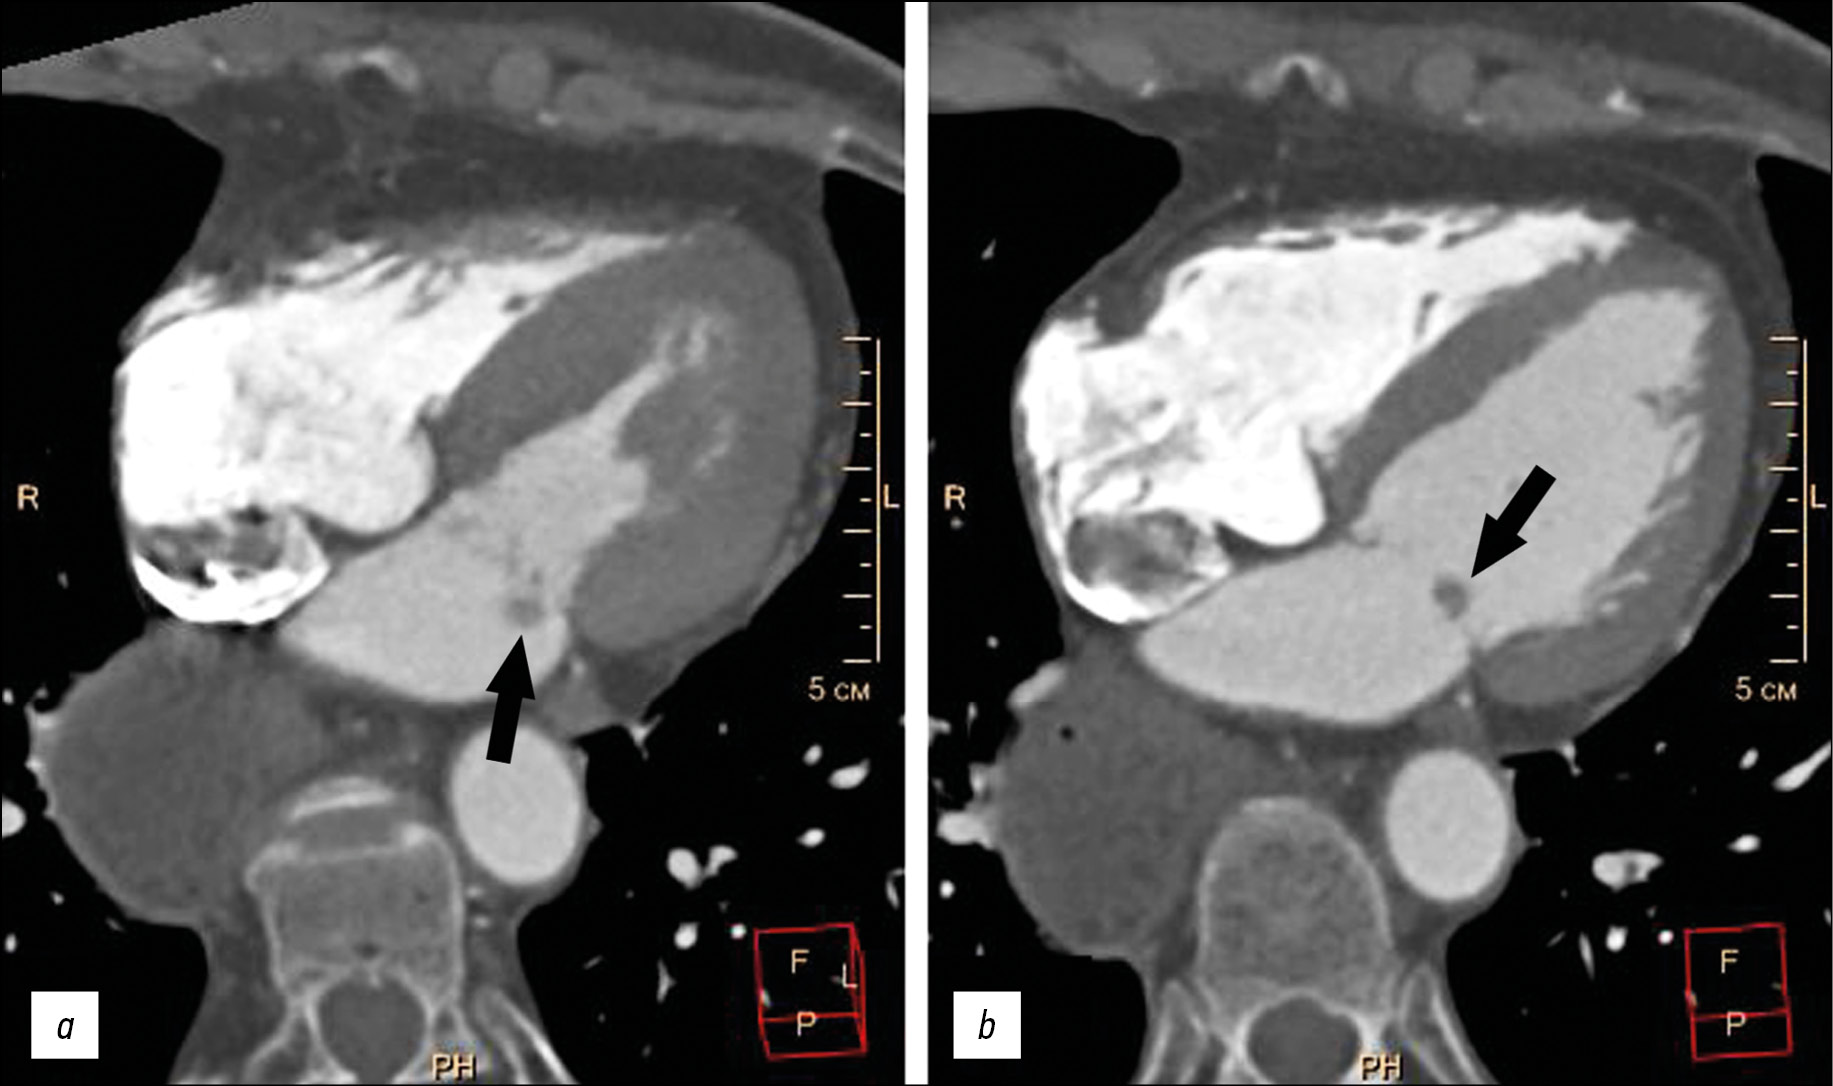

介绍了一名老年患者的病例,主诉喘息,左胸刺痛,心律失常,此患的病史包括吸引性肺炎,食管胃吻合术,食道摘除术。患者检查发现阵发性心房颤动(阵发外)、慢性心力衰竭、动脉高血压。患者的临床资料不具感染性心内膜炎特征,瓣膜上有赘生物。超声心动图和多螺旋计算机断层扫描在二尖瓣后叶的心房表面进行快速对比增强,显示额外的体积形成 5-9 毫米,圆形,轮廓明显不均匀,与瓣叶一起移位进入心房收缩期左心室腔。在Fiesta-CINE模式下,在修改后的两室和四室投影中获得了肿块的最佳可视化。患者在体外循环下接受了肿块的切除,并进行了二尖瓣成形术。肿块的组织学检查揭示了粘液瘤的特征性形态情况。术后期间一切顺利。